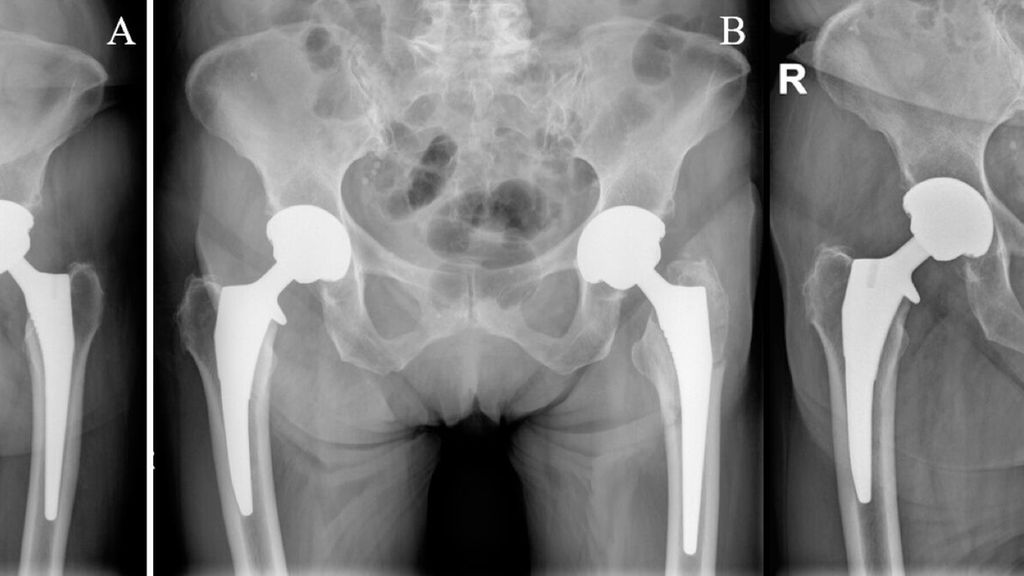

Seit 2015 werden an der Klinischen Abteilung für Orthopädie der Medizinischen Universität Wien nahezu immer zementfreie Schäfte mit Kragen verwendet. Noch nicht publizierte Daten unserer Abteilung zeigen ähnliche Ergebnisse, dass nämlich die Lockerungs- und Frakturrate beim Verwenden der Kragendesigns niedriger ist. Ein demonstratives Beispiel ist in Abbildung 1 zu sehen. Weitere radiologische und Migrationsanalysen werden derzeit vorgenommen.

Abb. 1: (A) Zustand nach beidseitiger zementfreier Hüfttotalendoprothese, rechts Kragendesign, links kragenloses Design; (B) auf der Seite mit kragenlosem Design kommt es zu einer periprothetischen Femurschaftfraktur links; (C) Systemwechsel auf tripolare Pfanne (aufgrund der Mehrfragmentfraktur im Bereich des Trochanter major) und auf einen diaphysär verankernden Schaft